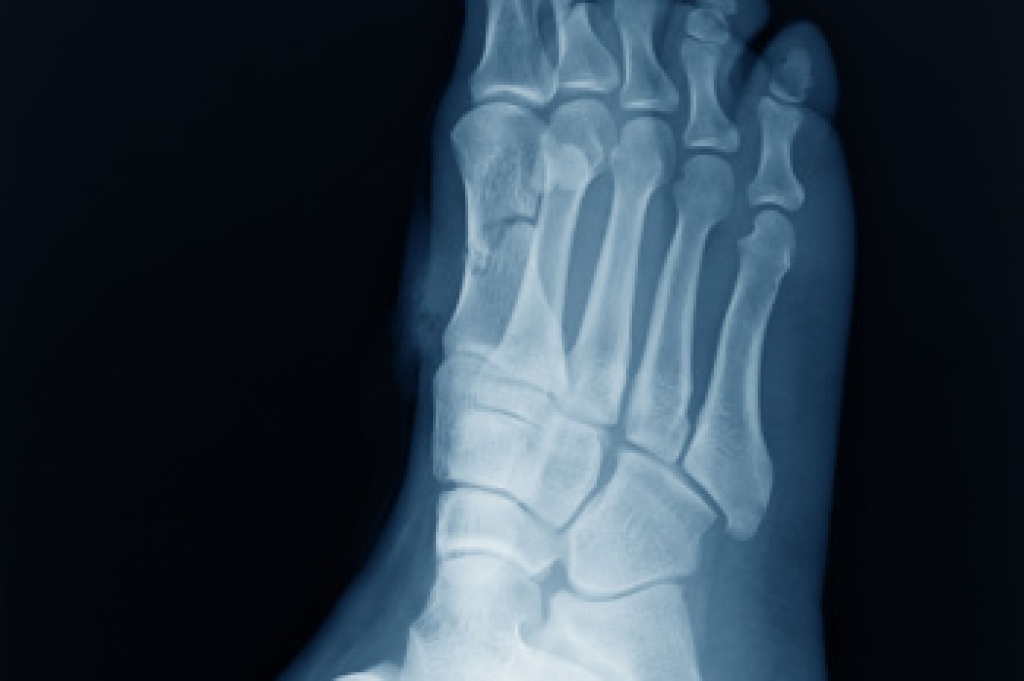

A Jones fracture and a pseudo Jones fracture both affect the long bone on the outer side of the foot near the little toe. However, these fractures happen in different areas and heal in different ways. A pseudo Jones fracture, also called an avulsion fracture, happens at the base of the bone. It often occurs when the foot twists inward and a tendon pulls off a small piece of bone. Because this area has better blood flow, it usually heals faster. A true Jones fracture happens a little farther down the bone. It is usually caused by a sudden twist, turn, fall, or repetitive overuse. That area of the foot has less blood supply, so healing takes longer and problems are more likely. Both injuries can cause pain, swelling, bruising, and trouble walking. A podiatrist can diagnose the problem with X-rays and provide the right treatment. If you have pain on the outer side of the foot, it is suggested that you schedule an appointment with a podiatrist for a diagnosis and appropriate treatment.

A broken foot is caused by one of the bones in the foot typically breaking when bended, crushed, or stretched beyond its natural capabilities. Usually the location of the fracture indicates how the break occurred, whether it was through an object, fall, or any other type of injury.

Treatment for broken bones varies depending on the cause, severity and location. Some will require the use of splints, casts or crutches while others could even involve surgery to repair the broken bones. Personal care includes the use of ice and keeping the foot stabilized and elevated.